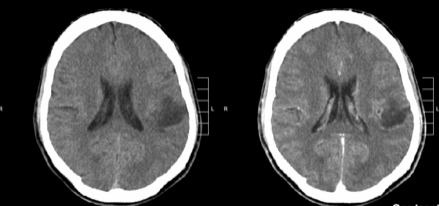

胶质瘤是起源于大脑的常见瘤种,大约40%-60%的脑瘤都是胶质瘤,它们起源于围绕并支持大脑神经元的神经胶质细胞,包括星形胶质细胞,少突胶质细胞和室管膜细胞。

大多数神经胶质瘤较初较好的治疗方法就是较大水平地手术切除,对于具有较高等级的神经胶质瘤的患者,手术后进行放射疗法和化学疗法。但许多脑胶质瘤通常发病在儿童期和青春期,在儿童肿瘤中占15%左右。对于儿童脑胶质瘤来说,由于手术损伤过大,并不是很好的选择。并且由于在脑中,手术治疗方法难以实施,所以放疗也是脑胶质瘤的主要治疗方法。其中,质子治疗对人的副作用比较小,而且治疗准确,特别用于治疗儿童高发的脑胶质瘤是更佳选择,很多脑胶质瘤患者都会选择进行质子治疗。那么,质子治疗胶质瘤效果好吗?

质子治疗胶质瘤效果好吗?INC国际神经外科医生集团旗下国际神经外科顾问团的诸多专家表示,大多数胶质瘤虽然优选治疗方法为手术,但许多脑胶质瘤发生在脑干及其桥脑等部位,由于位置深在,因其预后差,非手术可及,通常采用放疗作为标准治疗方法。但传统放疗一般要高剂量才能取得更好的治效果,这同时也增加了对邻近正常组织损伤的风险,特别是对于3岁以下儿童,放疗的辐射可能会对其发育产生长期影响。另外传统放疗是通过X光放疗和伽马刀进行治疗的,副作用很强,包括疲劳、头痛、脱发、恶心等。对儿童和老人的伤害较大,会严重影响儿童的生长发育和未来的身体状况。